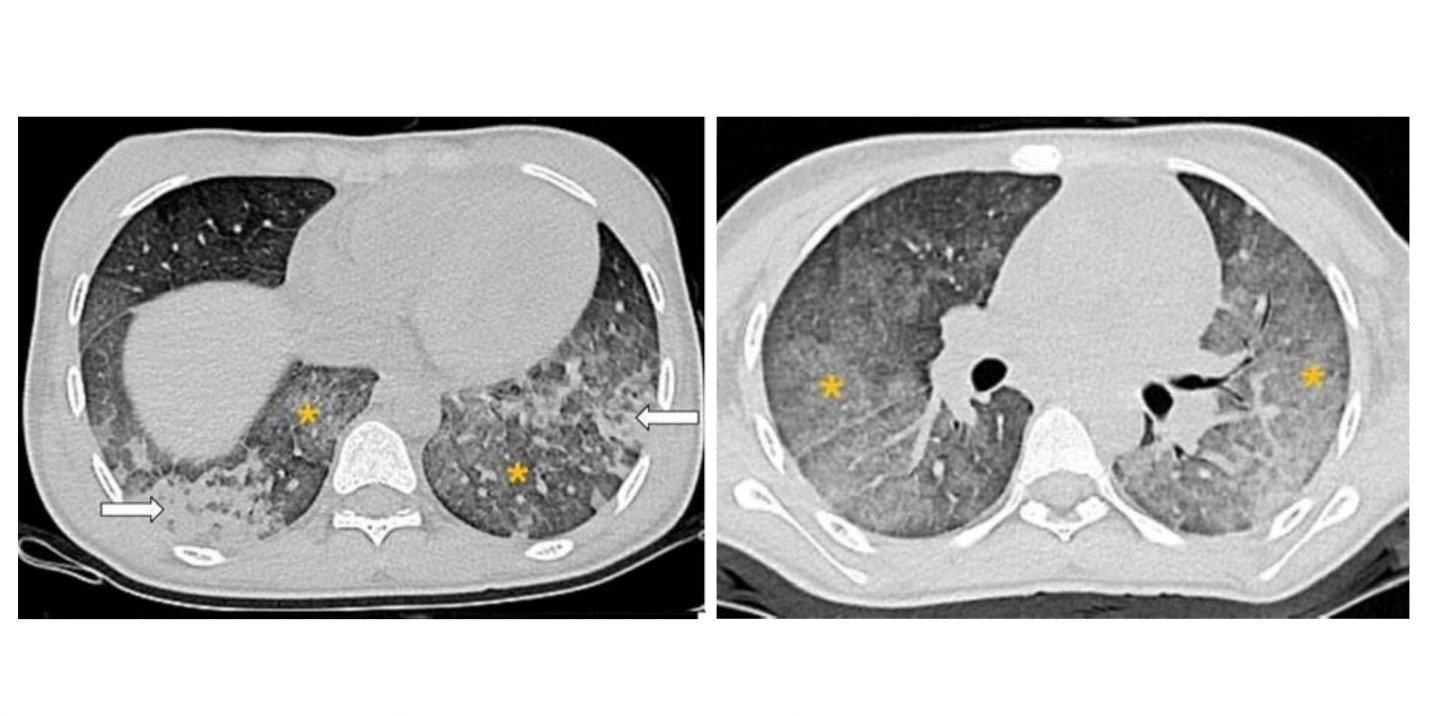

Hình ảnh chụp cắt lớp vi tính lồng ngực cho thấy hình ảnh các tổn thương gợi ý chảy máu phế nang lan tỏa. Ảnh BVCC

Chúng tôi nghĩ đến biến chứng chảy máu phế nang lan tỏa (DAH) ở bệnh nhân SLE. Đây là một biểu hiện hiếm gặp, chỉ khoảng 2% số ca SLE ở trẻ em. Khi xảy ra, DAH thường diễn tiến rất nhanh gây suy hô hấp cấp, thiếu máu nặng và có thể tử vong nếu không được điều trị kịp thời.